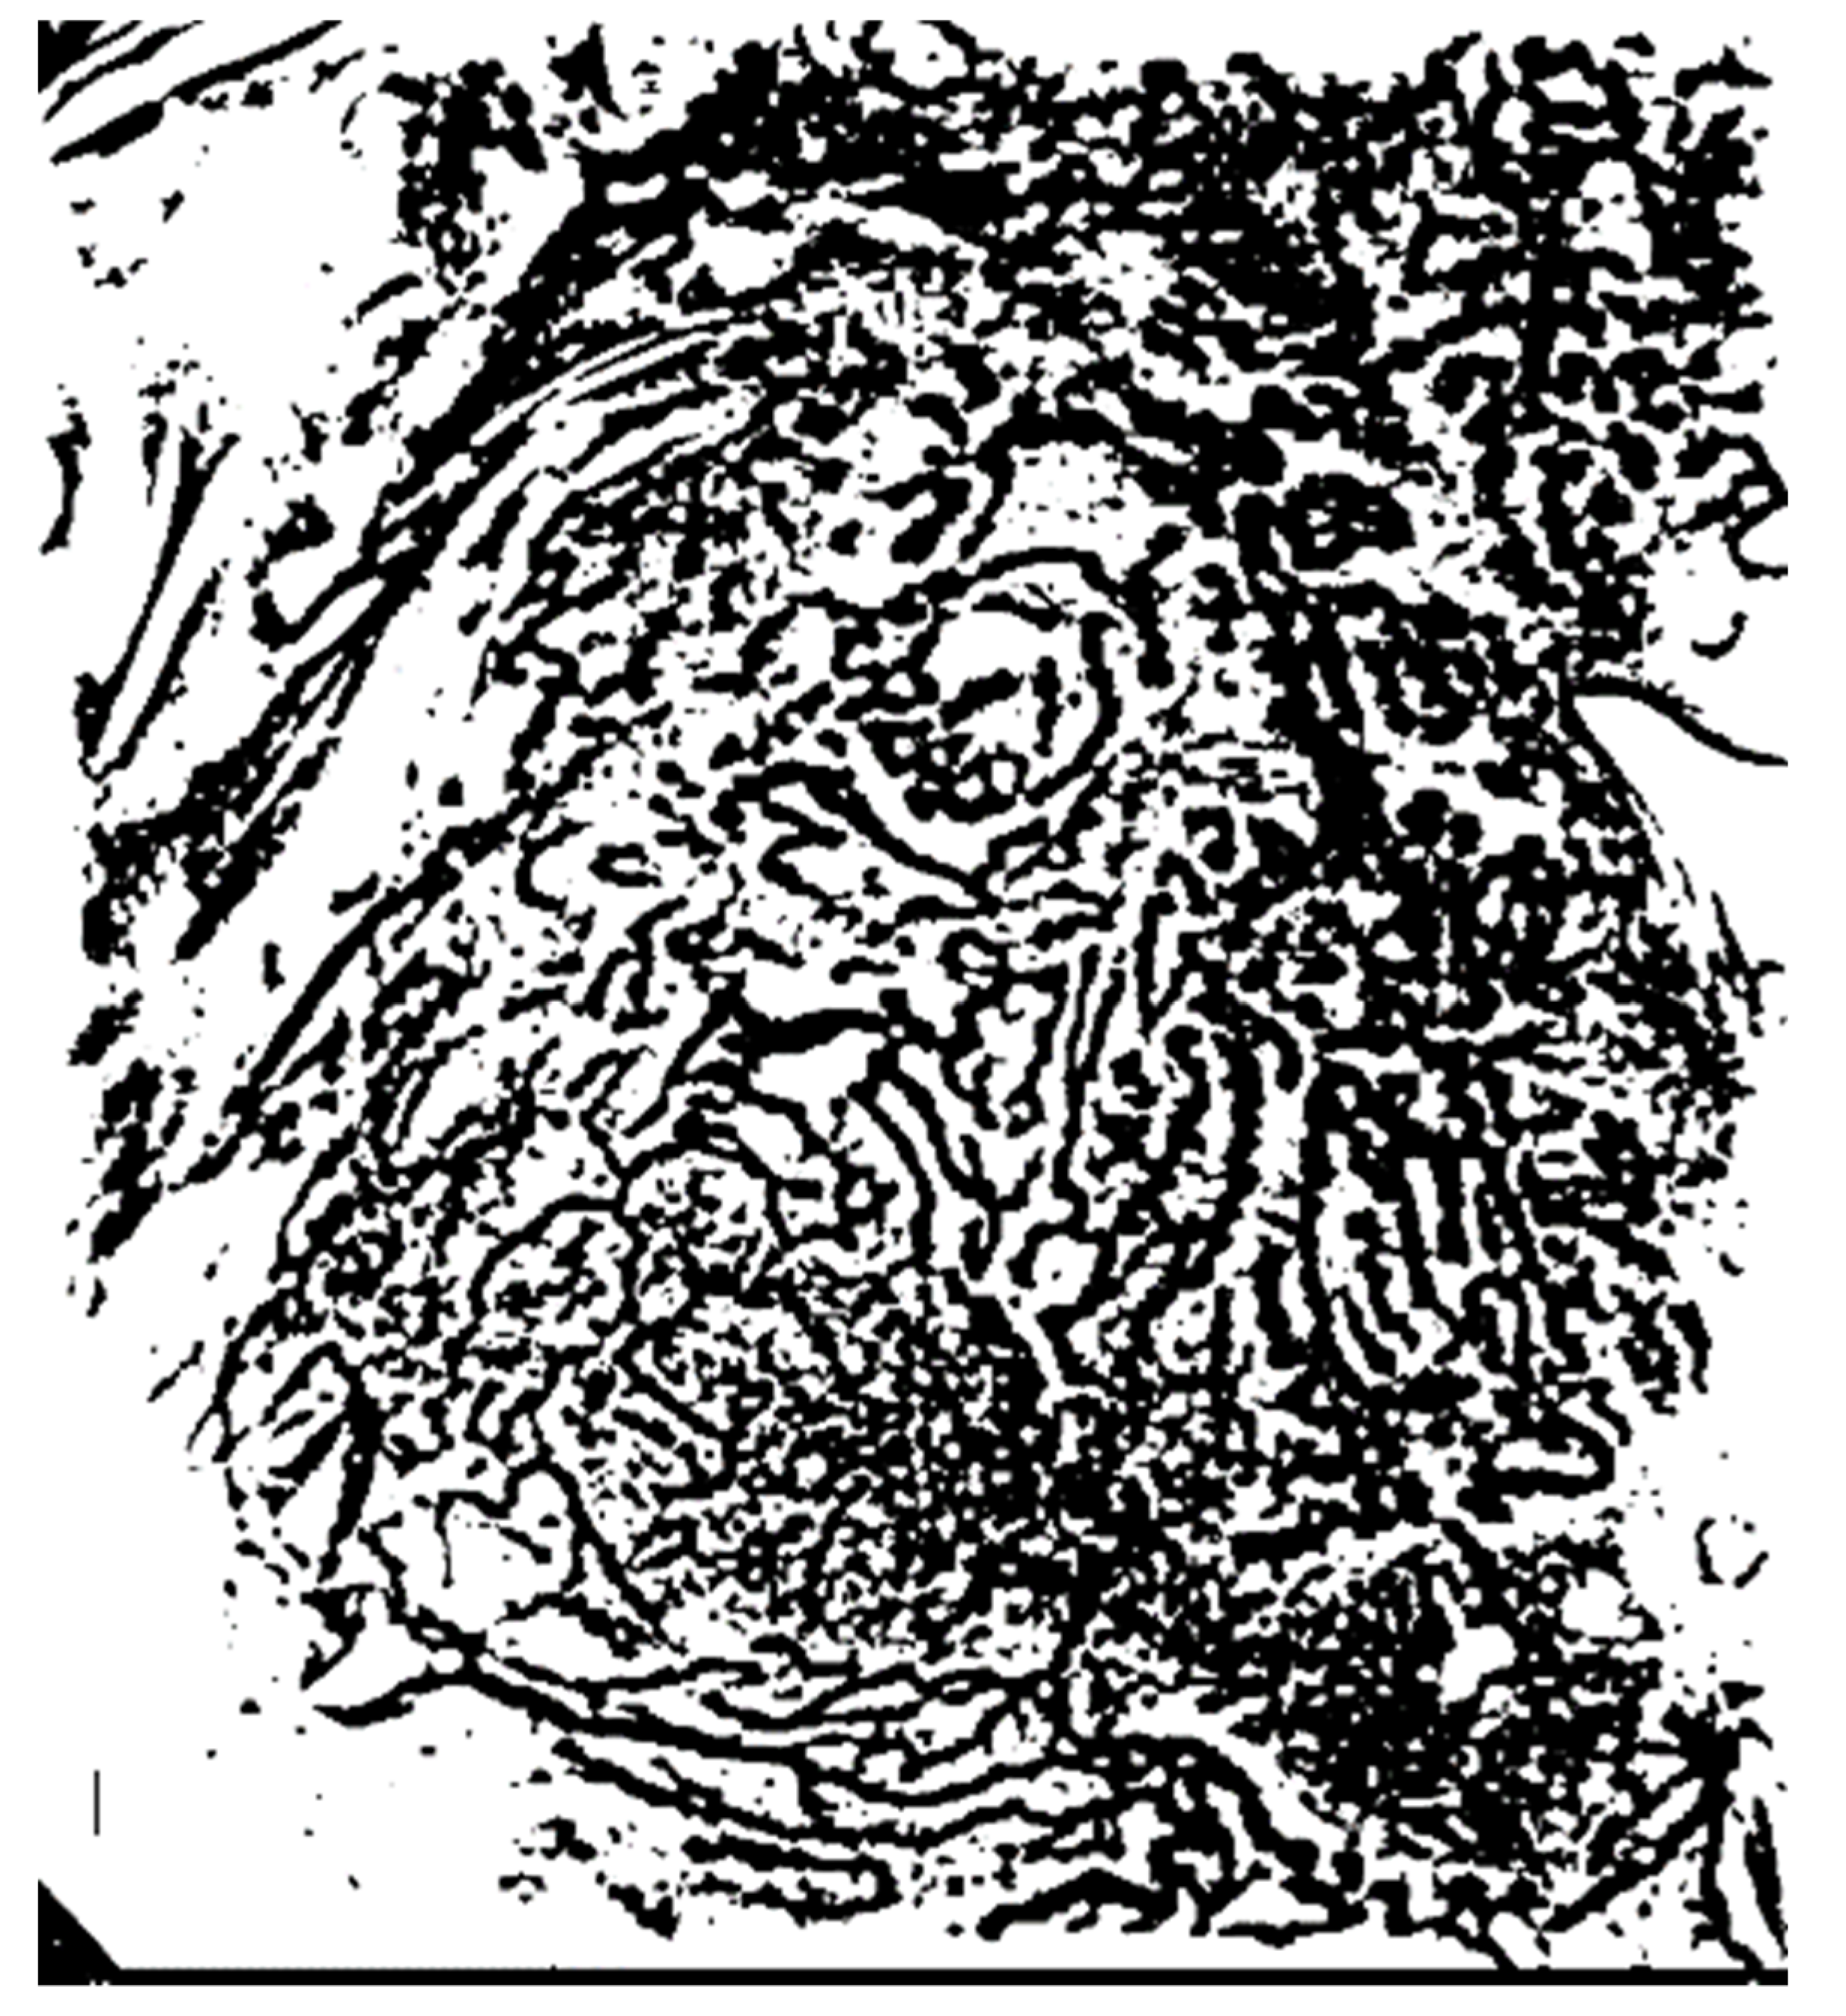

3.2.3. Removal of the Background Area Using the ART2 Algorithm

3.3. Extraction of Object Information from the Microvessel Area